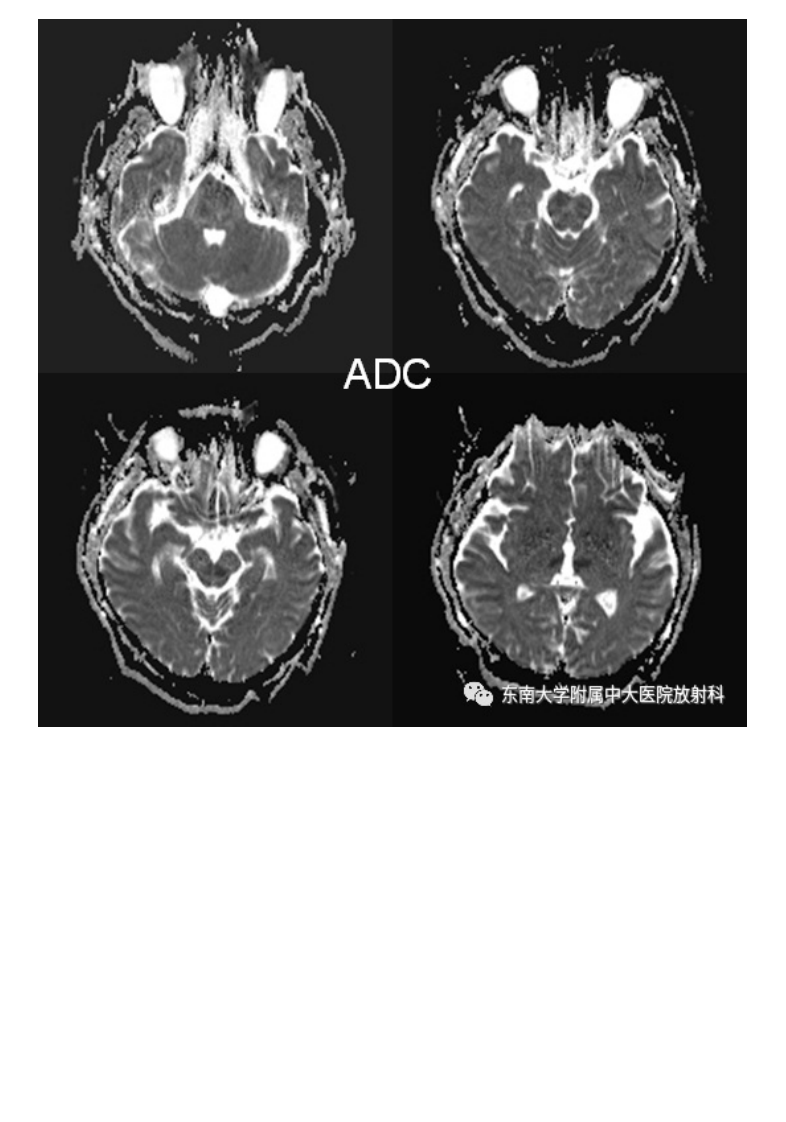

20210509_3【晨读结果公布】2021.05.08神经系统疾病——基底动脉尖综合征.pdf